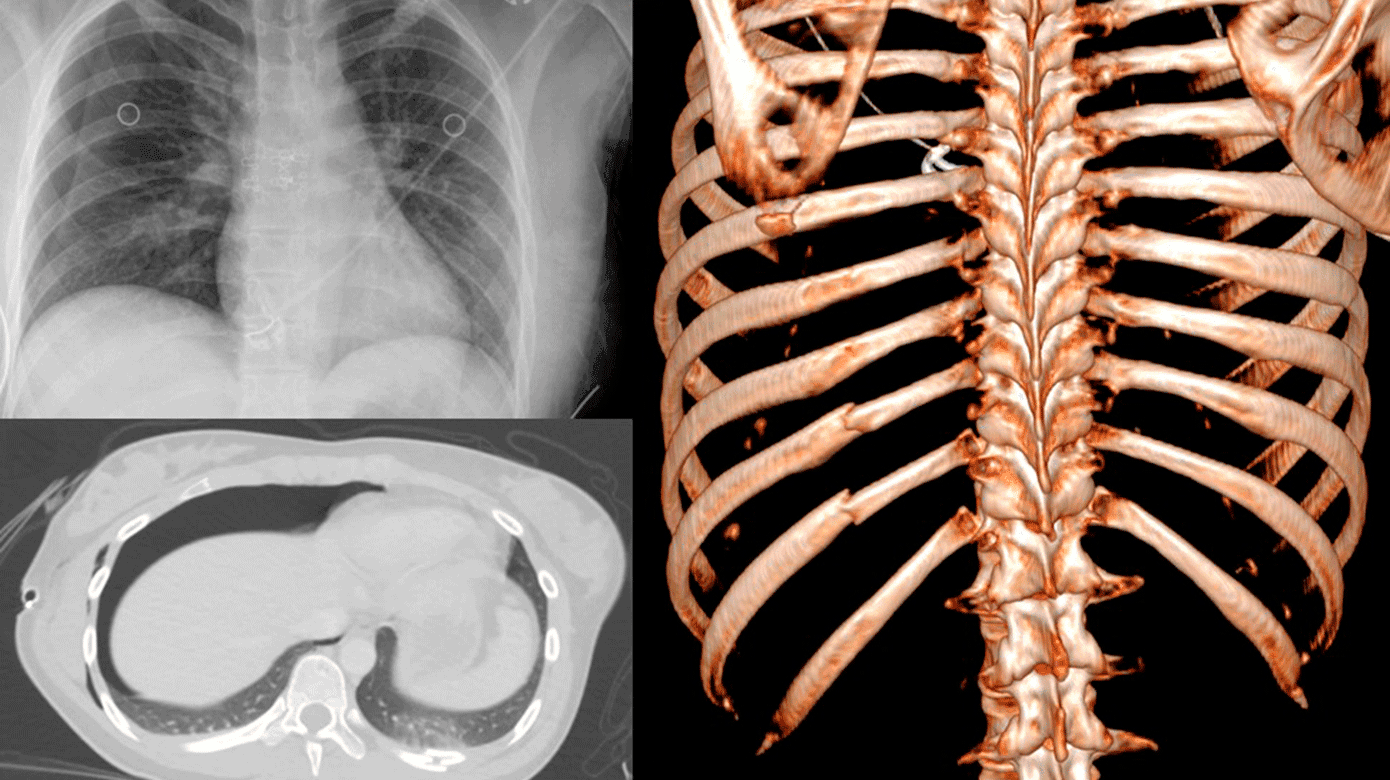

På røntgenundersøgelse af thorax fandtes en stor højresidig pneumothorax (Figur 1 A), hvorfor der blev anlagt højresidigt pleuradræn. Der var ikke tegn på trykpneumothorax. Traume-CT viste frakturer i venstre costae 8-12 (Figur 1 B og C) samt multiple øvrige frakturer i venstre side af kroppen og ustabile bækkenfrakturer med involvering af sacroiliacaleddet og os sacrum. I abdomen fandtes kontusion af venstre nyre og pancreas. Der var ingen skader på milten og ingen hovedskader. Der kunne ikke erkendes costafrakturer på højre side, hvor der sås pneumothorax, og omvendt var der ikke pneumothorax på venstre side, hvor patienten havde mindst fem costafrakturer. Der var ikke pneumomediastinum.

Pleuradrænet blev seponeret 16 timer efter anlæggelse, og på kontrolrøntgenundersøgelse sås stort set fuld regression af pneumothorax. På CT udført dagen efter var der fortsat ingen synlige costafrakturer højresidigt.